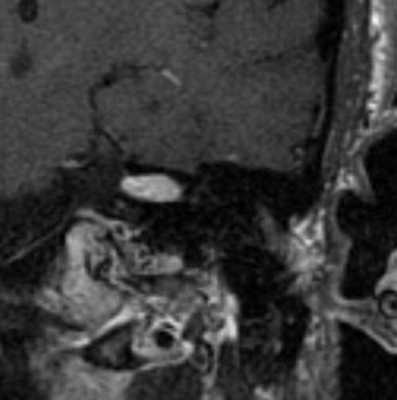

МРТ головного мозга. Т1-взвешенная корональная МРТ с контрастированием. Полностью внутриканальцевая невринома.

Вестибулокохлеарный нерв (VIII) состоит из 4 пучков. Опухоли происходят обычно из вестибулярной его части. Шваннома - инкапсулированная доброкачественная (градация 1) опухоль, происходящая из дифференцированных неопластических шванновских клеток оболочек периферических нервов. Невриномы ММУ составляют около 3% опухолей головного мозга. Часть шванном (двухсторонние слуховых нервов) связана с НФ 2 типа. Пик частоты между 40 и 60 годами. Растут медленно и крайне редко малигнизируются. Клинические проявления связаны с нарушением функции нерва и компрессией ствола. Шваннома может происходить из любого отрезка по ходу нерва и хорошо прослеживается при МРТ области ММУ. Невринома видна как на Т2-взвешенных, так и на Т1-взвешенных МРТ в виде округлого образования. Невриномы хорошо и равномерно усиливаются после МРТ с введением контрастного вещества. Невриномы области цистерны могут иметь компонент во внутреннем слуховом проходе, особенно, хорошо видимый при МРТ головного мозга с контрастированием. Изредка встречаются невриномы полностью расположенные внутри канальца. Они составляют наибольшую диагностическую сложность при МРТ, требуют тонких срезов и контрастирования. Менингиомы ММУ обычно типично расположены и при МРТ имеют характерную форму и типичные черты при МРТ с контрастированием. Однако редко встречаются внутриканальцевые менингиомы. При МРТ они неотличимы от неврином. Холестеатомы при МРТ имеют смешанную интенсивность сигнала, в зависимости от их содержимого. На диффузионно-взвешенных МРТ холестеатомы обычно яркие.

МР-сканирование при подозрении на менингиому мостомозжечкового угла, сагиттальная проекция